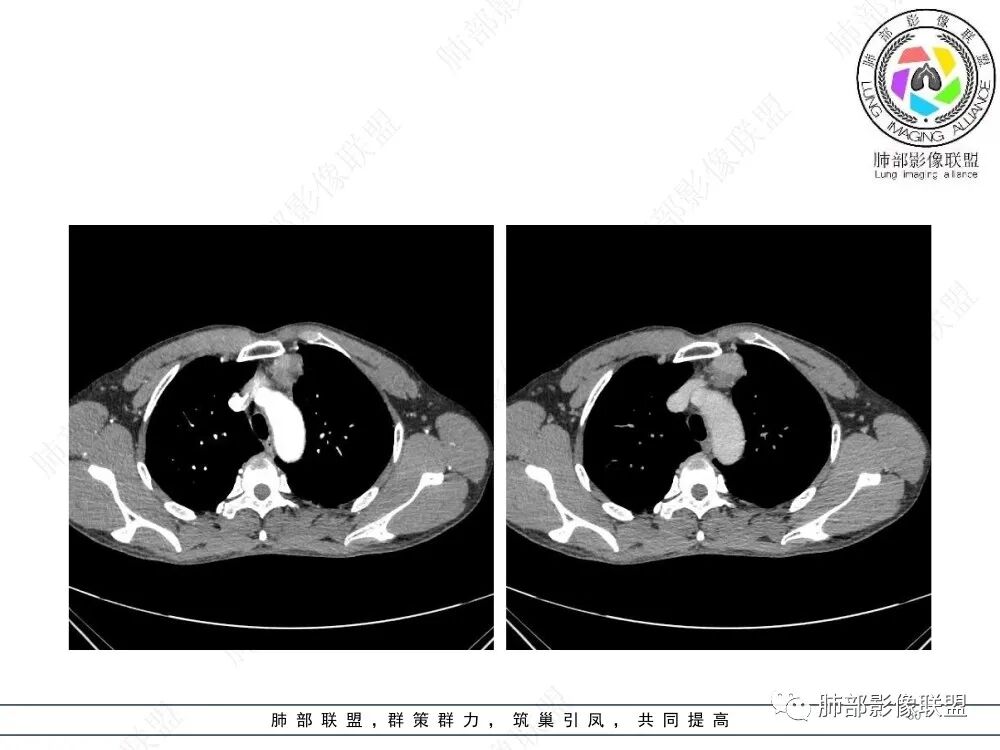

衡妈🇨🇳:中年男性,前纵隔偏左侧实性占位,密度相对均匀,边缘分叶,周围脂肪结构略模糊,增强后动脉期不均匀强化,有低密度区,纤维分隔显示不清。考虑胸腺瘤B1 B2型。

朱伟超:中年男性,前纵膈偏离中线肿块,浅分叶,内有分隔,中等不均匀强化,常规胸腺瘤。

流心明智:男,47,咳嗽、咳痰1年余。胸部CT:前纵膈偏左类圆形肿块,瘤肺界面清晰光整,纵隔侧部分层面絮状影?平扫密度较均匀,增强后轻度强化,内可见宽带及线样低密度分隔。邻近左上肺受压凹陷。考虑胸腺肿瘤,AB型?胸腺Ca?鉴别淋巴瘤、N源性肿瘤、CD等。

在路上:考虑胸腺瘤,密度均匀,无钙化,轻度强化,边缘请放射线:前纵膈偏左侧肿块,边缘光滑清晰,周围脂肪间隙清晰,渐进性强化,密度不均,考虑胸腺瘤,鉴别淋巴瘤。

良孑:前纵隔肿物,偏心性生长,轻分叶,均勺强化,内可见分格,支持AB型胸腺瘤。

lmg:前纵膈肿块,整体边界整齐,可见AB区,强化不均匀,可见延时强化,病灶内未见明显钙化,无分叶,考虑AB型胸腺瘤。

2、影像特点:前纵隔偏左侧软组织影,密度相对均匀,未见明显包膜钙化及实质内钙化,局部边缘浅分叶,周围脂肪间隙密度增高、浑浊,未见侵犯大血管、未见纵隔内淋巴结转移、未见侵犯心包内结构、未见胸膜转移结节、未见肿块沿着纵隔胸膜蔓延,未见胸腔积液。增强后动脉期不均匀强化,未见明显纤维分隔。